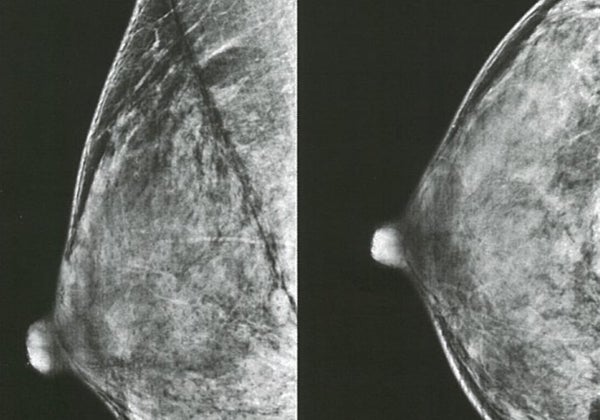

De todos los cánceres, es el de mama el que el mayor número de casos de 'aparición temprana' ha experimentado. Detrás de este tumor se sitúan los cánceres de tráquea (nasofaringe) y de próstata, que son los que más han aumentado desde 1990.

Los datos muestran que en 2019, los nuevos diagnósticos de cáncer entre los menores de 50 años ascendieron a 1,82 millones, un aumento del 79% respecto a la cifra de 1990. En general, el cáncer de mama representó el mayor número de estos casos y muertes asociadas, con 13,7 y 3,5/100.000 de la población mundial, respectivamente.

Más de un millón (1,06) de menores de 50 años murieron de cáncer en 2019, lo que supone un aumento de algo menos del 28% respecto a la cifra de 1990. Después del cáncer de mama, los cánceres que causaron el mayor número de muertes y el consiguiente deterioro de la salud fueron los de tráquea, pulmón, estómago e intestino, con los aumentos más pronunciados de muertes entre las personas con cáncer de riñón u ovario.

EE.UU. y Europa cambian sus recomendaciones para la primera mamografía: ¿Cuándo hay que hacerla entonces?

Nuria Ramírez de CastroLas nuevas guías estadounidenses aconsejan empezar a los 40 años en lugar de a los 50. El plan europeo del cáncer pide no solo adelantar sino extender el chequeo hasta los 75 años